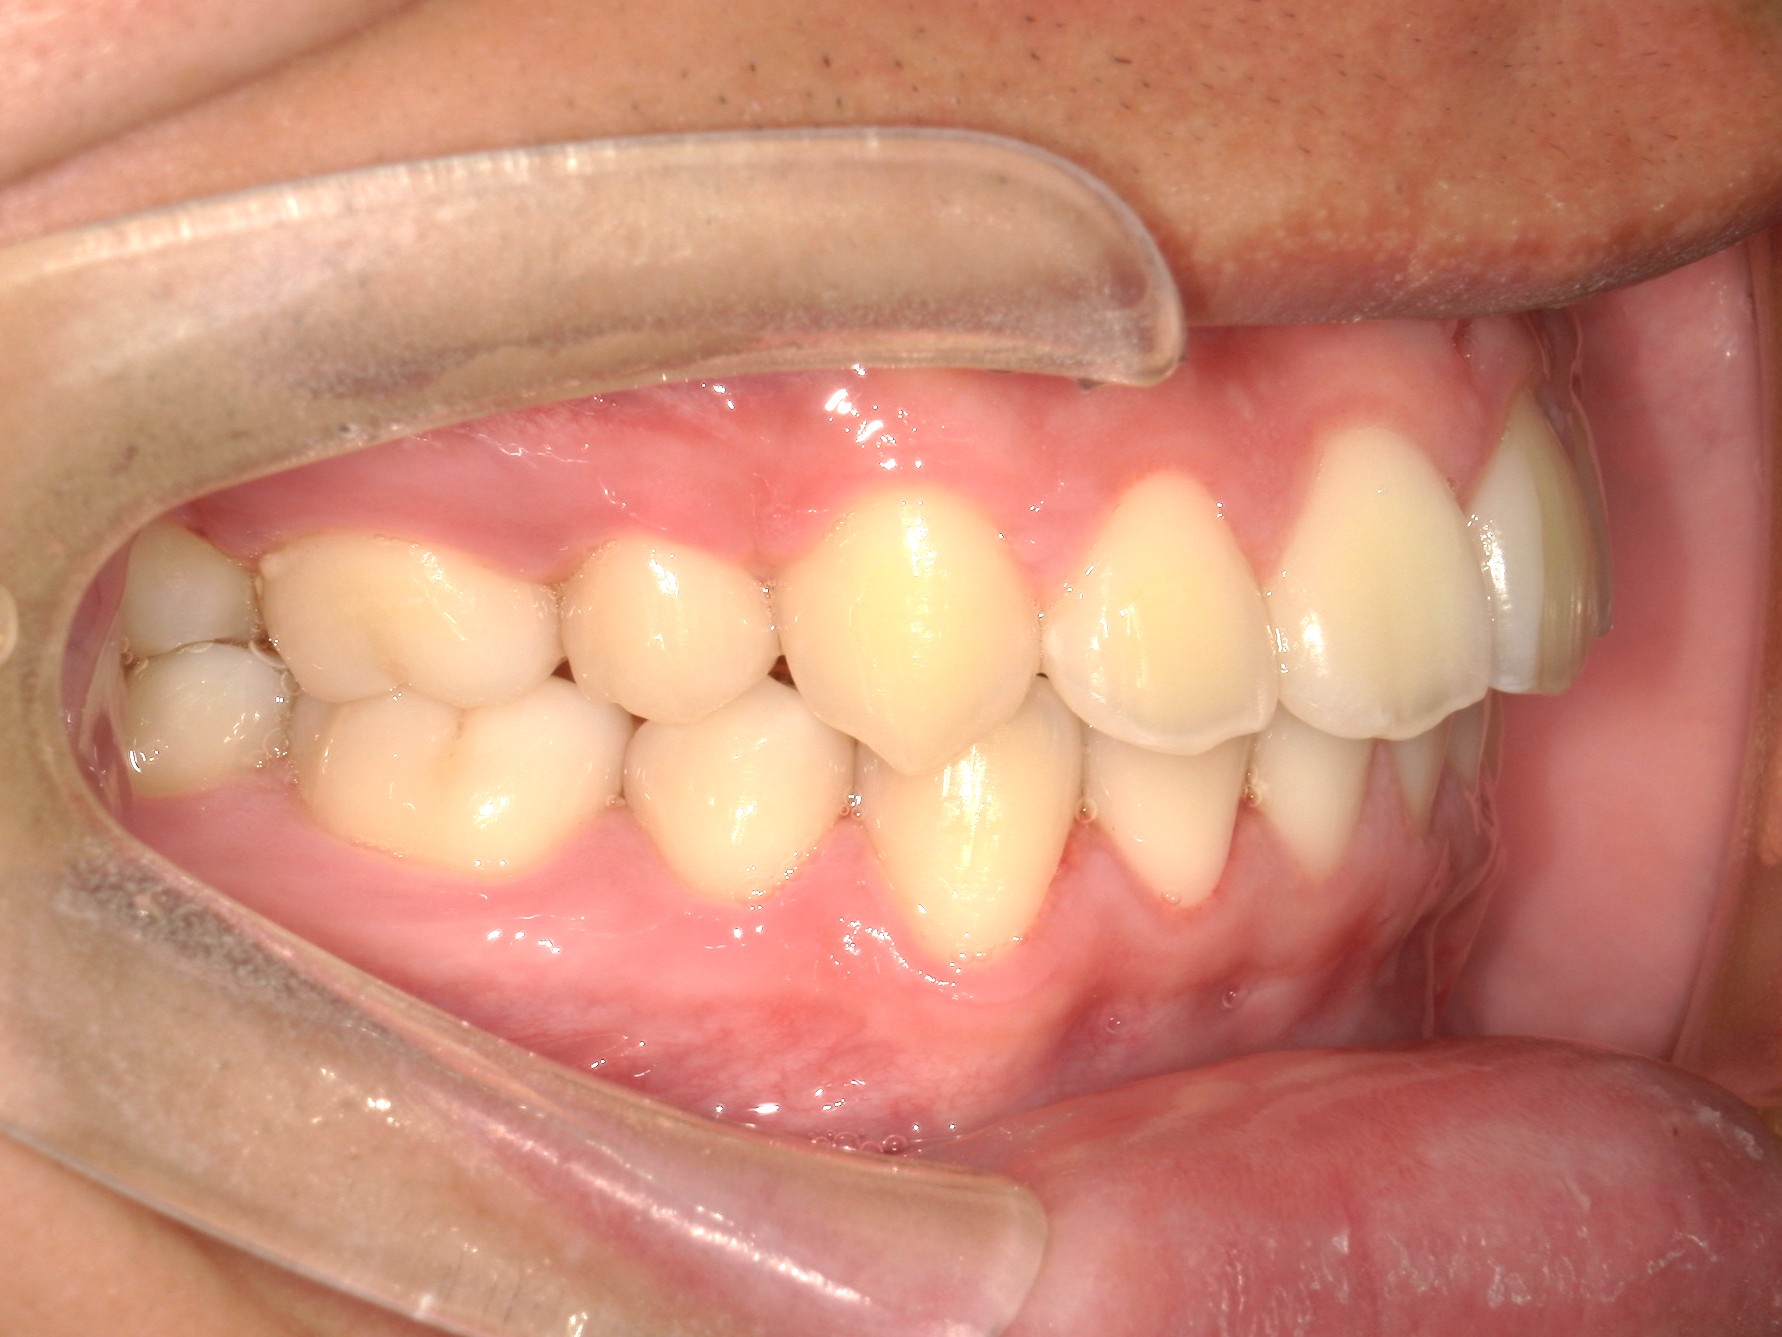

口内右

治療前

治療後